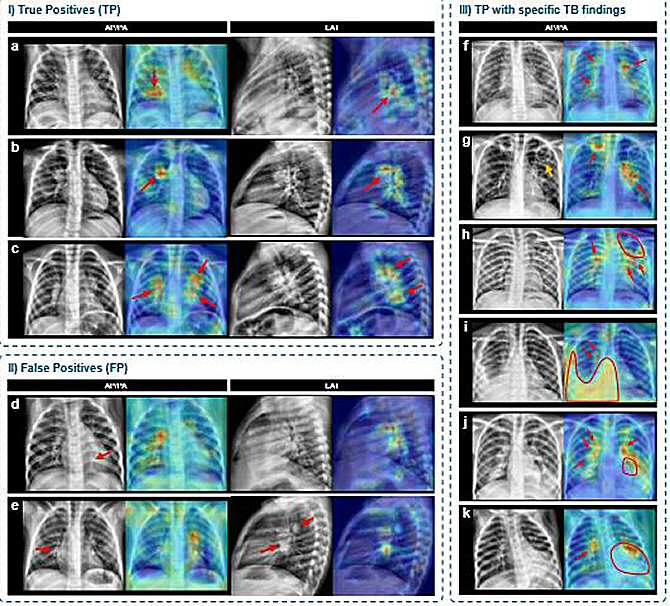

Mapas de activación generados mediante técnicas de explicabilidad que señalan las regiones de interés utilizadas por el modelo de inteligencia artificial para tomar sus decisiones sobre las radiografías. (Imagen: equipo de investigación / UPM)

Además de los resultados cuantitativos, el equipo incorporó técnicas de inteligencia artificial explicable que generan mapas visuales señalando las zonas de la radiografía que influyeron en cada decisión. Estas representaciones facilitan la revisión clínica de las predicciones y aumentan la confianza en el uso asistido por inteligencia artificial.